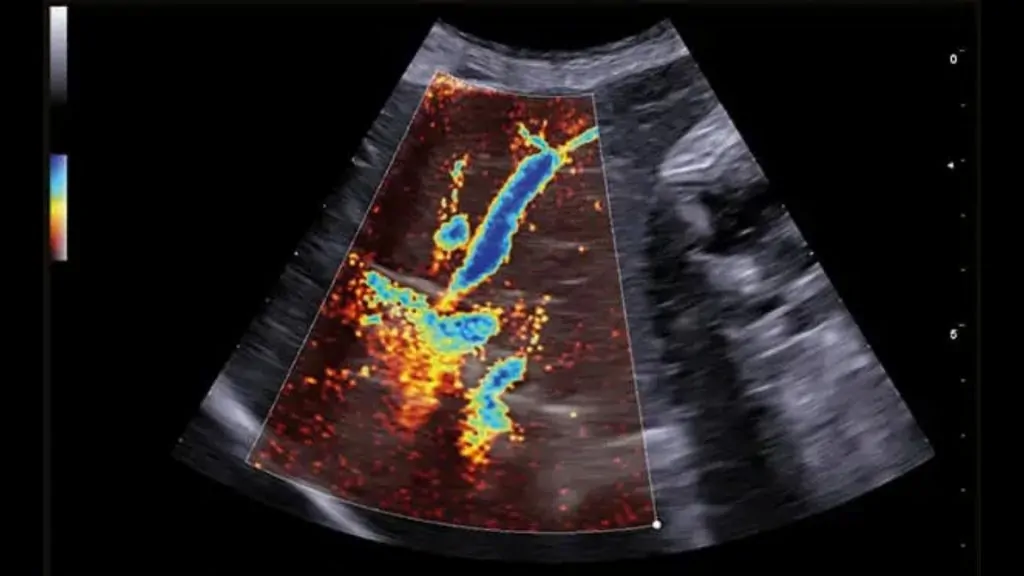

Ekokardiyografi (EKO), veteriner hekimlikte kalp hastalıklarının tanısı, derecelendirilmesi ve takibinde kullanılan en değerli görüntüleme yöntemlerinden biridir. Yüksek frekanslı ses dalgaları ile kalbin kapaklarını, odacıklarını, kas yapısını ve kan akımını gerçek zamanlı değerlendirmeye olanak sağlar.

Kalp hastalıklarında yalnızca “var/yok” yanıtı değil; hastalığın şiddeti, kalbin çalışma performansı ve ilerleyişi hakkında sayısal ve klinik olarak kritik bilgiler sunar. Bu nedenle birçok kardiyovasküler problemde EKO, tanısal yaklaşımın temel basamağıdır.